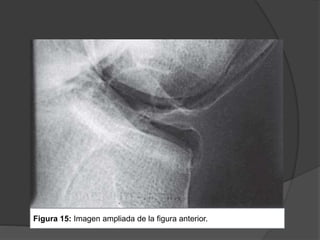

Figura 14: Artrografía

de la rodilla con

contraste doble.

Figura 15: Imagen ampliada de la figura anterior.

Figura 15: Imagenampliada de la figura anterior.